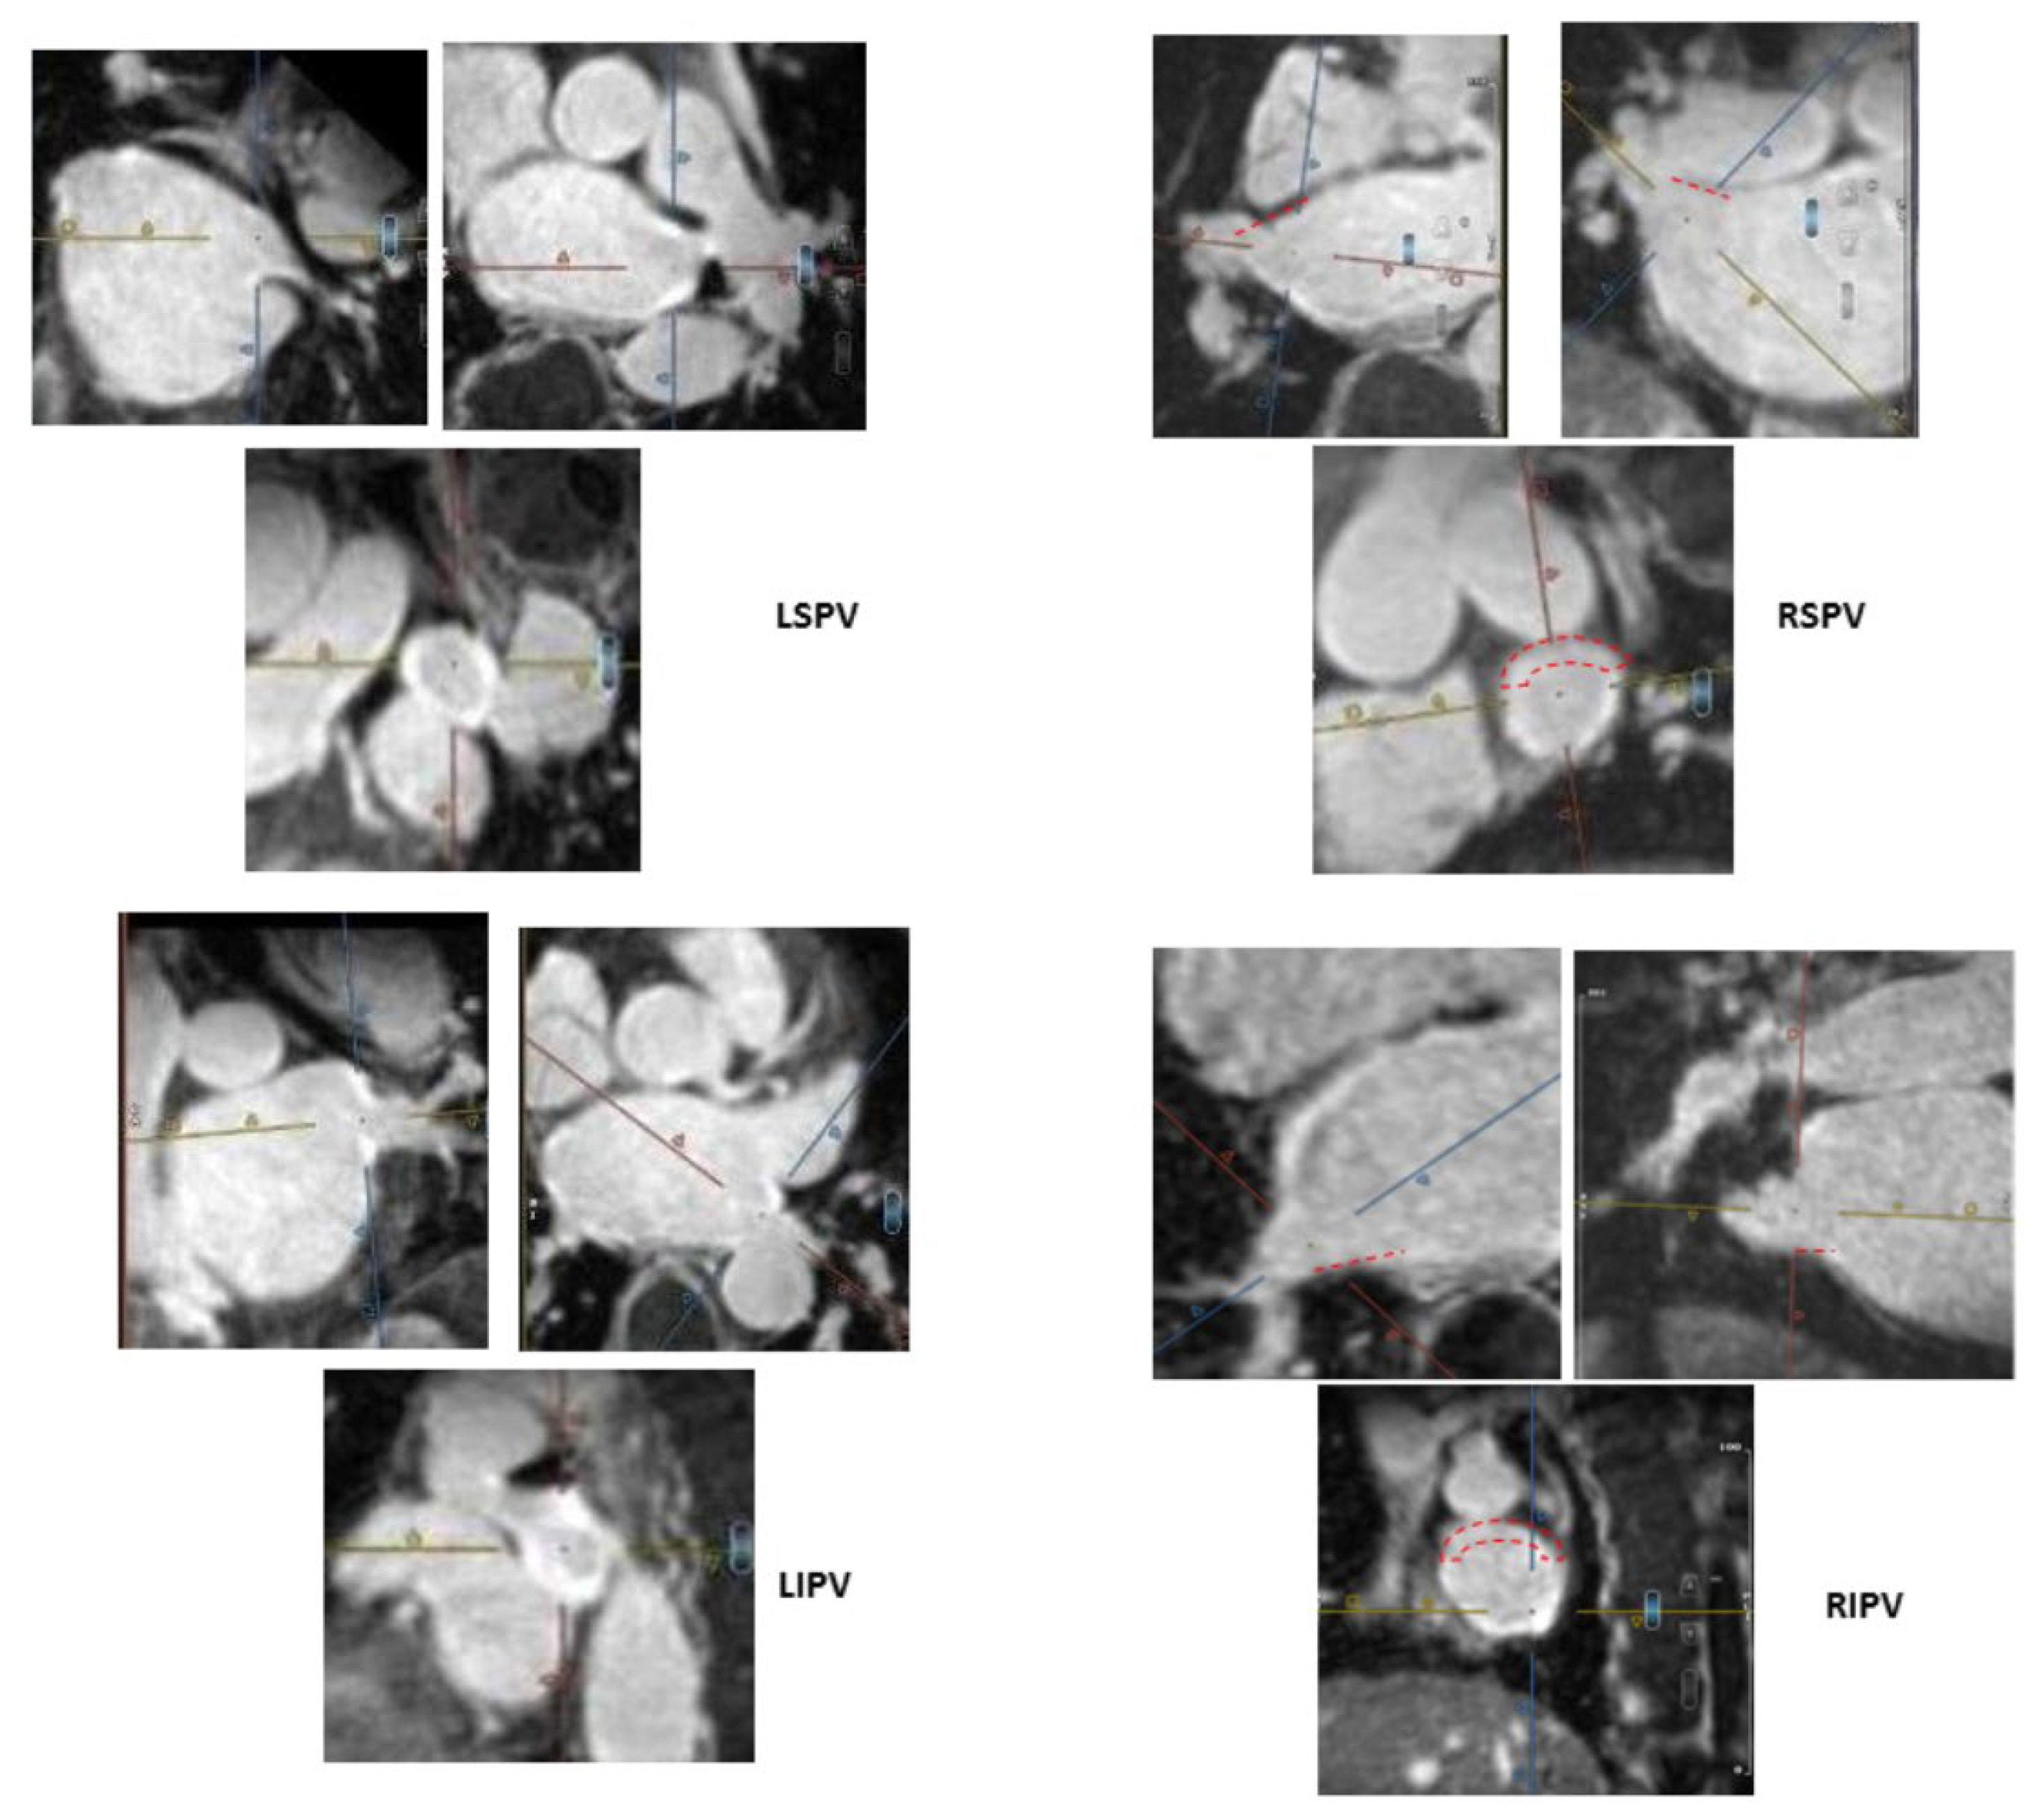

) and thus are defined as partial incomplete circumferential PV ostial fibrosis. The right PV gaps are marked (

) both on the orthogonal plane images and the cross-sectional view.